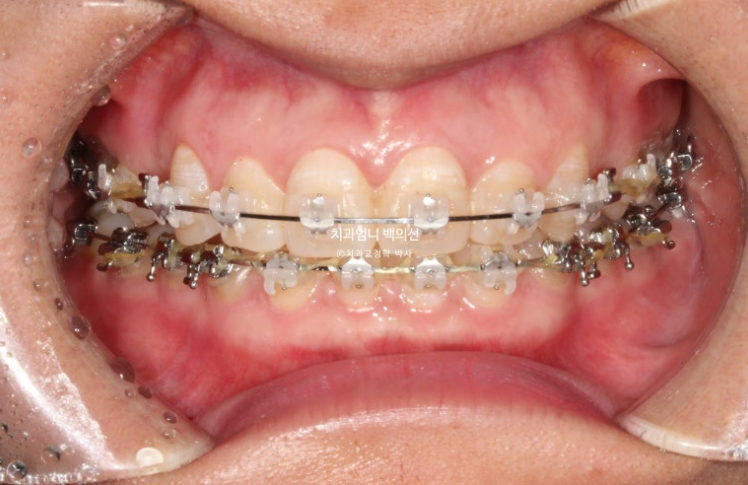

24.07

치료시작 10개월째 모습입니다.

상악 발치공간이 보입니다.

아래는 송곳니를 앞니자리로 끌어오는 중입니다.

환자분이 30대임에도 치아이동속도가 빠른 편이였고